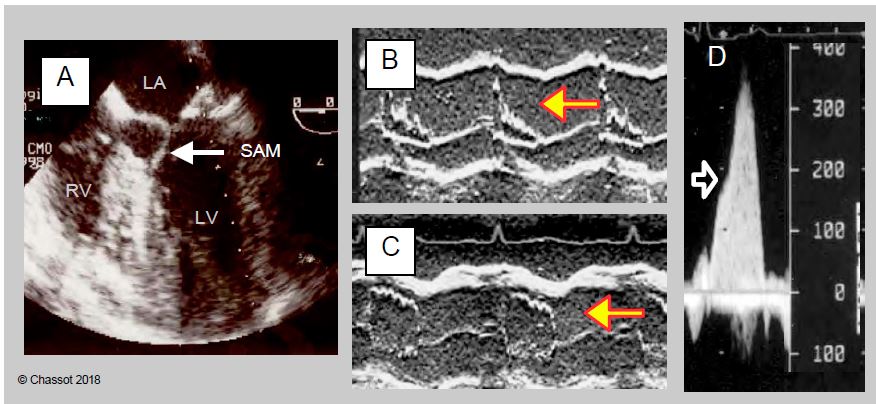

When the coaptation point of the mitral valve moves towards the LVOT, the occlusion is no longer on the distal edge of the anterior leaflet but on its body, and the intaventricular pressure pushes it anteriorly towards the outflow tract in protosystole. Due to the Venturi effect, it is then pulled into the LVOT and occludes it more or less completely. This is the SAM (systolic anterior motion) that occurs in meso-tesystole (Figure 11.57). The flow in the aorta decreases and the reopening of the mitral valve during systole causes a meso-tesystolic MI. This phenomenon is clearly visible in the 4-cavity, 5-cavity view or long-axis mid-esophageal LV.

Fig11 57 en

Figure 11.57: Systolic anterior motion (SAM) of the anterior leaflet after mitral valve repair; 5-view HOCM image of SAM; the two white arrows indicate the position of the prosthetic annulus; the yellow arrow shows the displacement of the distal part of the anterior leaflet into the LV outflow tract (LVOT).